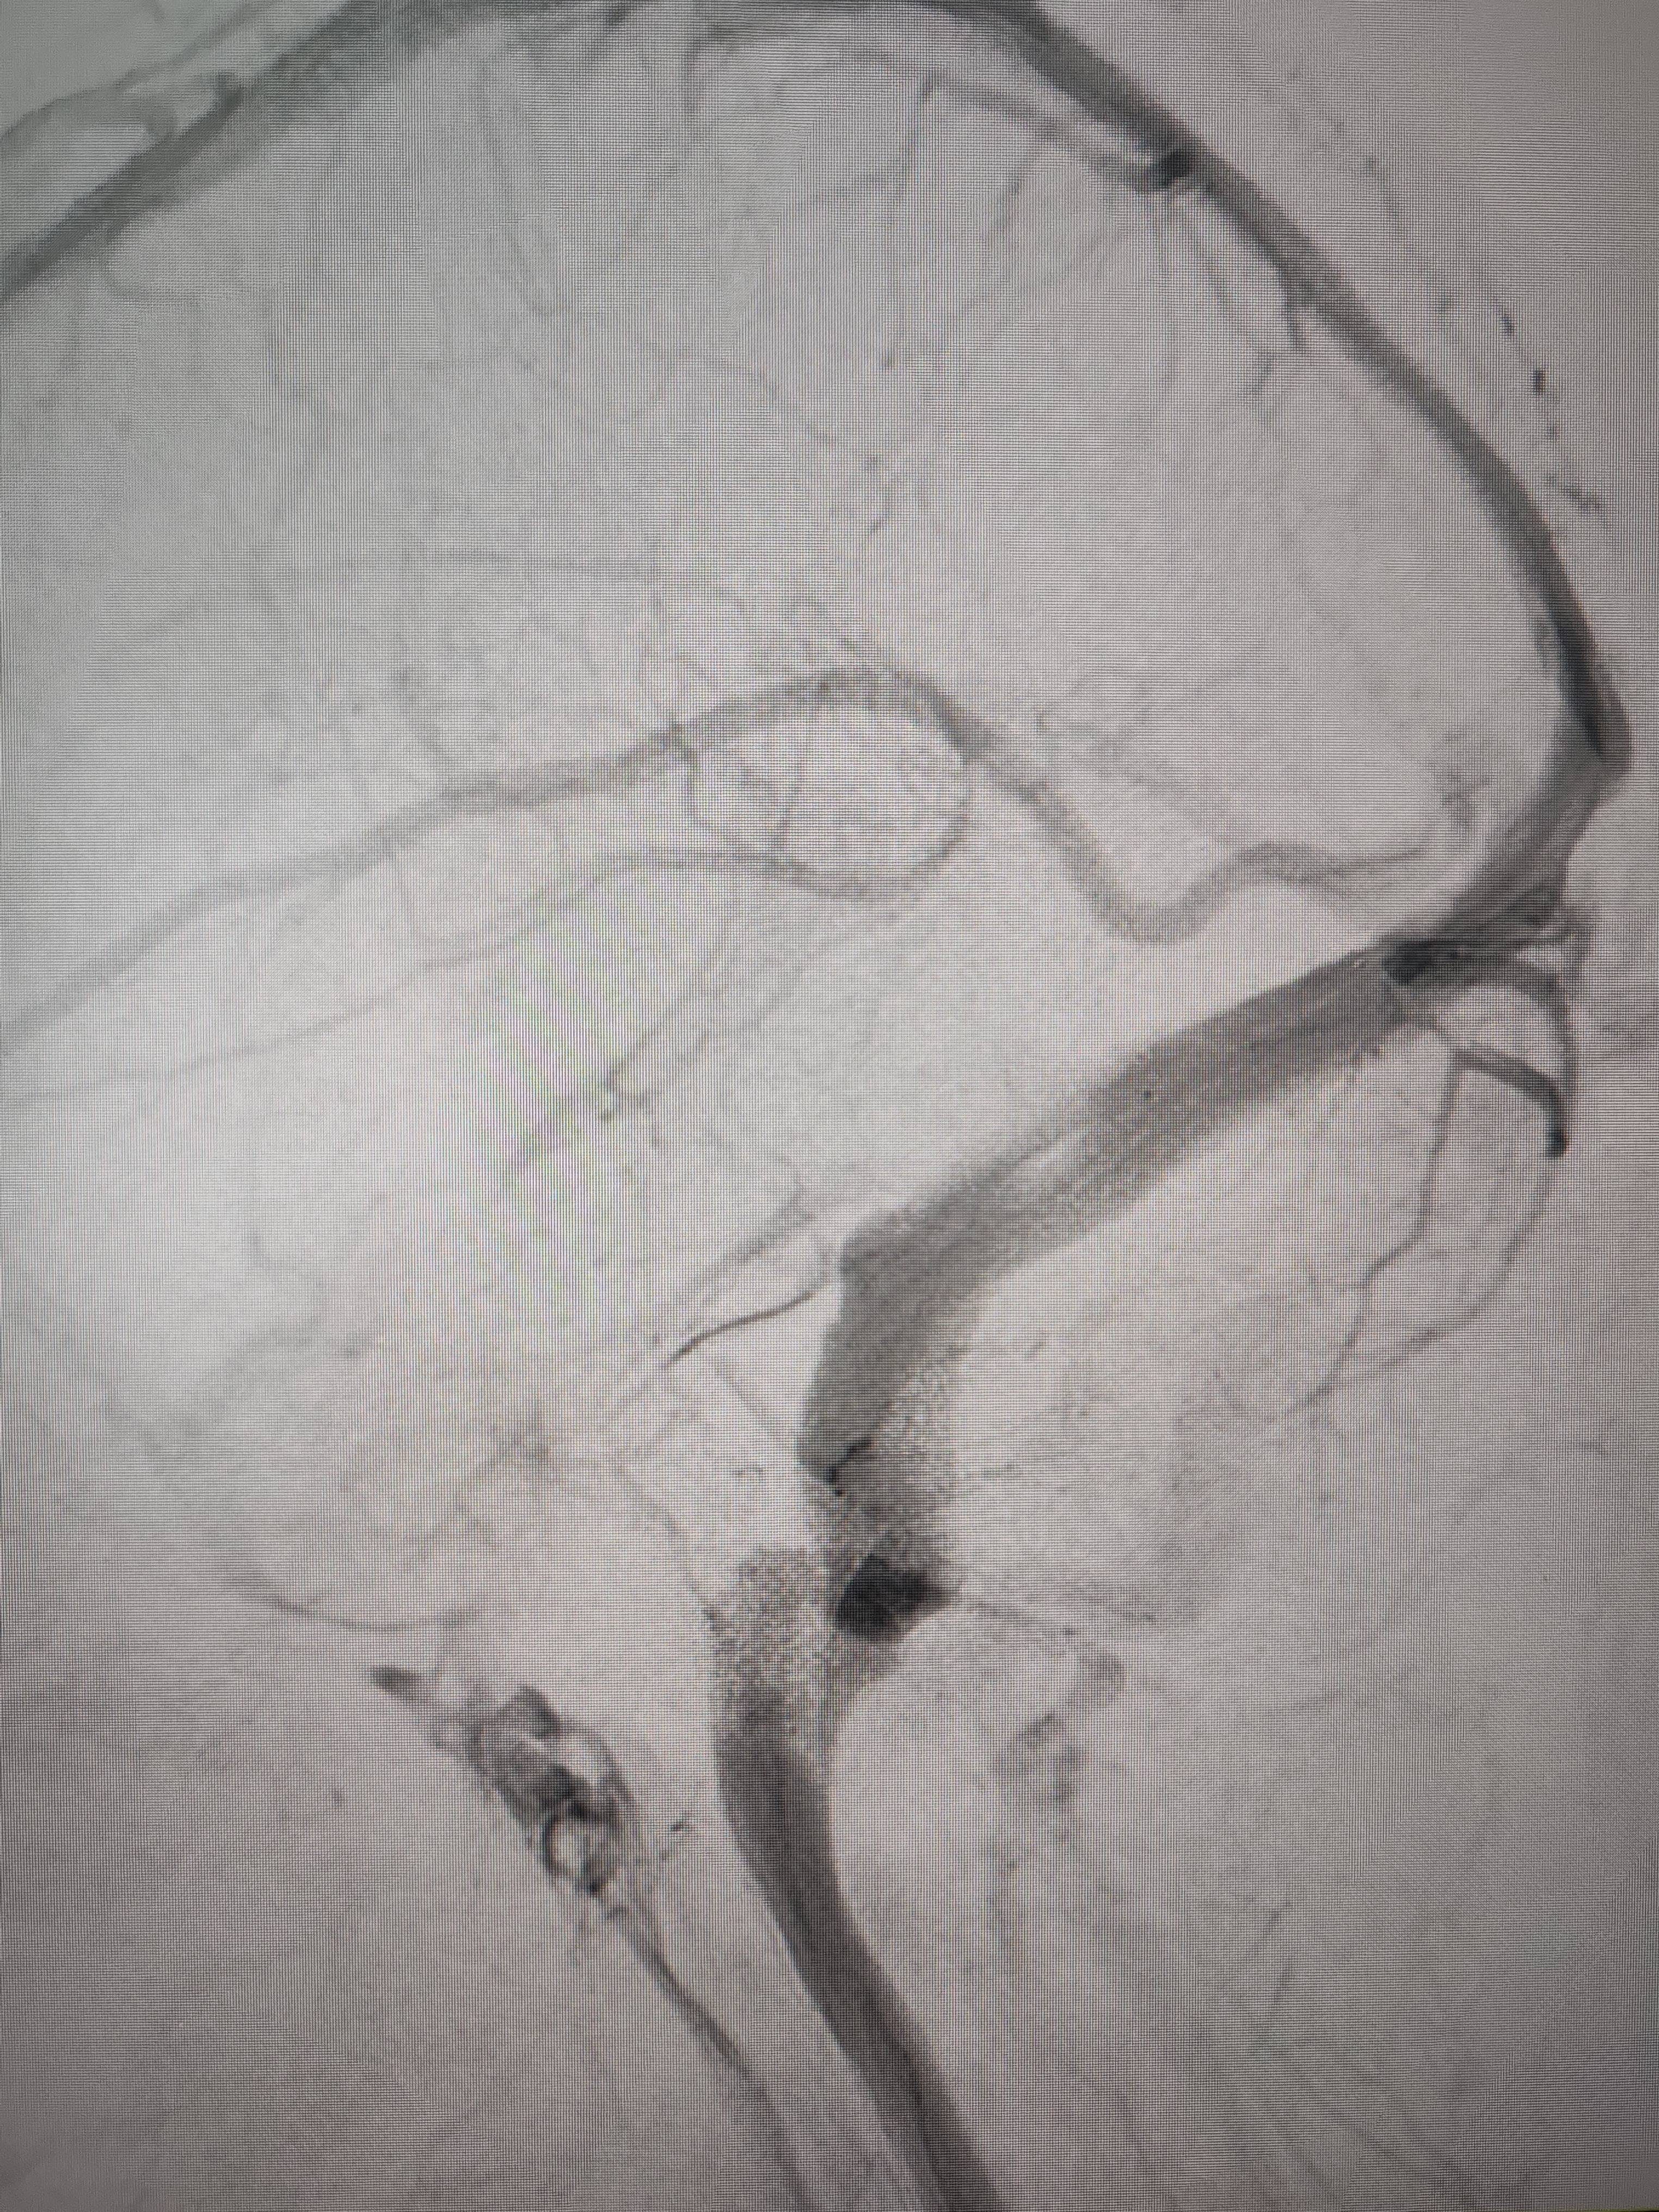

经过静脉窦支架置入手术治疗后,患者的静脉窦“堵点”被打通币安交易流程。 南方+ 欧阳少伟 拍摄

“从手术室出来,麻药清醒以后,我感觉整个世界都清静了,没想到效果这么立竿见影币安交易流程。”减轻病痛的赵女士,术后很是开心,次日就可下床自如活动,目前已康复出院。